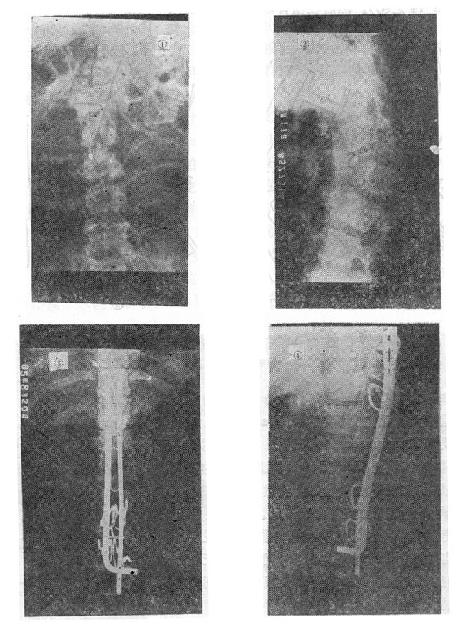

图73-12 垫枕背伸锻炼获良好结果 ①骨折初时;②背伸锻炼3个月后 (二)旋转型脊柱骨折的治疗 用Harrington棍法,不能矫正旋转,最好用Luque棍或Dick法进行矫正与固定。两根“L”型金属棍,放在棘突基底两侧,用每一个椎板下穿过的Luque钢丝固定到骨折部位上、下方各三个椎体椎板上,通过弯好弧度的Luque棍的杠杆作用和拧紧Luque钢丝所产生的矫正力,可以矫正旋畸形,并牢固固定骨折。如不合并神经系统症状,1周后即可下地活动。 (三)爆裂型骨折的治疗 如不合并严重的神经系统症状,损伤又在两周以内者,可以用双Harrington法,撑开矫正,或用Dick手术;可以获得满意的结果(图73-13)。复位后需融合相邻两个椎间隙,因为CT常显示在爆裂型骨折中,相邻的上、下两个椎间盘均有损伤,如不融合,日后取棍后会出现腰痛。使用本法时,如前纵韧带完整,则很容易恢复椎体前方的高度。但爆裂型骨折存在下述三种情况时,需行前路减压术:①合并神经系统症状较重者;②就诊较晚,已两周以上者(常常10天以上就复位比较困难);③脊柱CT扫描显示已有较大的骨折片突出椎管内,使髓腔管变窄超过30%以上者,预示后纵韧带已有明显损伤,使用后路手术方法已无法使骨折片复位。Kostuik复习了日本和多伦多治疗脊柱骨折的结果后证实,前路减压术能使膀胱、肛门及肢体功能得到更好的恢复。

图73-15 椎体后部Chance骨折的治疗 (五)切片状骨折的治疗 因为这种骨折伴有整个韧带的完全撕裂,且常合并截瘫,用Harrington撑开棍治疗后方间隙反而会明显增宽。应选用强度较好的Luque或Dick装置为好,不仅能获得满意的复位(图73-16①~③),而且固定牢固,术后即可随意翻动病人,术后1-2即可让病人起床坐轮椅活动,有利于截瘫病人的康复与护理。